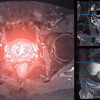

Izin bertanya dok. Banyak orang melakukan skrining kanker prostat secara mandiri dengan memeriksa PSA. Sebenarnya, apakah metode skrining ini sudah terbukti bermanfaat untuk mengurangi mortalitas akibat kanker prostat? Pasien seperti apa sajakah yang sebaiknya dianjurkan untuk skrining kanker prostat berkala? Terima kasih, Dok.